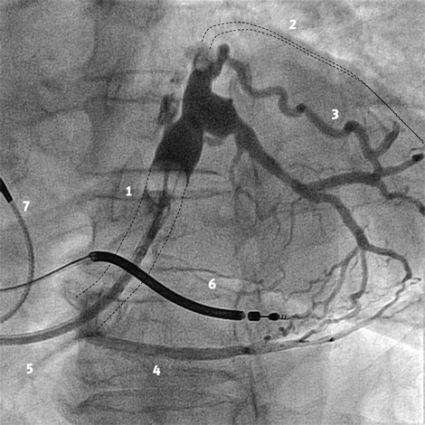

CRT-implantationen är ett tekniskt krävande ingrepp som för optimalt resultat kräver stor vana och bör förbehållas centra med stor volym. I dag görs ingreppet vanligen i lokalanestesi, och vänsterkammarelektroden placeras transvenöst. I vissa fall kan dock epikardiella elektroder placeras kirurgiskt genom en torakotomi. Vid en transvenös rutinprocedur kateteriseras sinus coronarius med hjälp av en speciell, lång införingshylsa. Ett venogram utförs med en ballongkateter för att kartlägga hjärtats venanatomi. En speciell pacingelektrod förs in i en epikardiell ven från vilken vänster kammare kan stimuleras. Det lämpligaste kärlet är oftast sinus coronarius posterolaterala gren. Stimuleringsläget väljs rutinmässigt inte utifrån hemodynamisk effekt utan beroende på de tekniska pacingparametrarna sensing- och tröskelvärde.